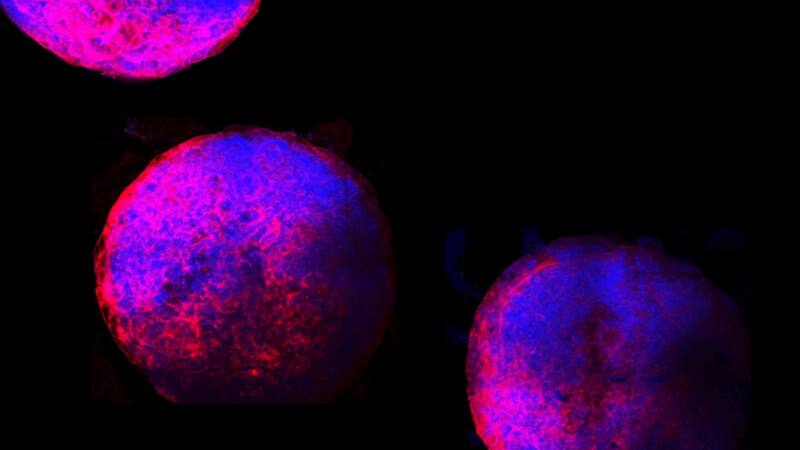

No son más grandes que las semillas de sésamo y pulsan con un ritmo hipnótico. Estos son “minicorazones” humanos, los primeros que se crearon en el laboratorio con cámaras que palpitaban claramente.

Después de 1 semana de desarrollo, los organoides son estructuralmente equivalentes al corazón de un embrión de 25 días. En esta etapa, el corazón tiene solo una cámara, que se convertirá en el ventrículo izquierdo del corazón maduro. Los organoides miden aproximadamente 2 milímetros de diámetro e incluyen los principales tipos de células típicamente presentes en esta etapa de desarrollo: cardiomiocitos, células epiteliales, fibroblastos y epicardio. También tienen una cámara claramente definida que late de 60 a 100 veces por minuto, la misma frecuencia del corazón de un embrión alrededor de la misma edad, informó el equipo en la revista científica Cell.

“Cuando lo vi por primera vez, me sorprendió que estas cámaras pudieran formarse por sí mismas”, mencionó la autora principal Sasha Mendjan, bióloga de células madre del Instituto de Biotecnología Molecular de la Academia de Ciencias de Austria. “Lo sorprendente es que ves inmediatamente si el experimento funcionó y el organoide es funcional, ya que late, a diferencia de otros órganos”.